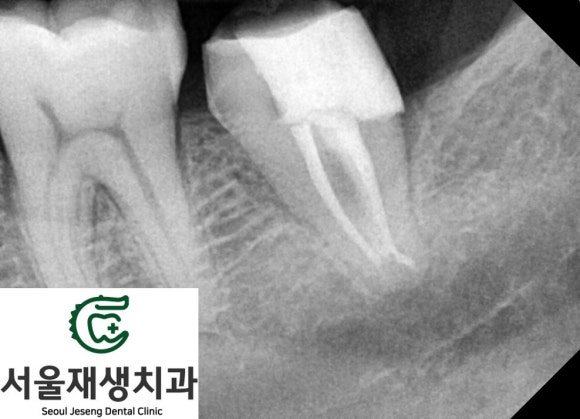

신경치료의 마무리는

크라운으로 튼튼하게!

자연치와 유사한 심미성을 가진

지르코니아 크라운 (=도자기 크라운)을

씌워서 치아를 향후 발생할 파절로 부터

보호해주었습니다.

환자분께서 다행히 시간 여유가 있으셔서,

열흘 남짓한 시간에 모든 치료가

신속하게 진행되었습니다.